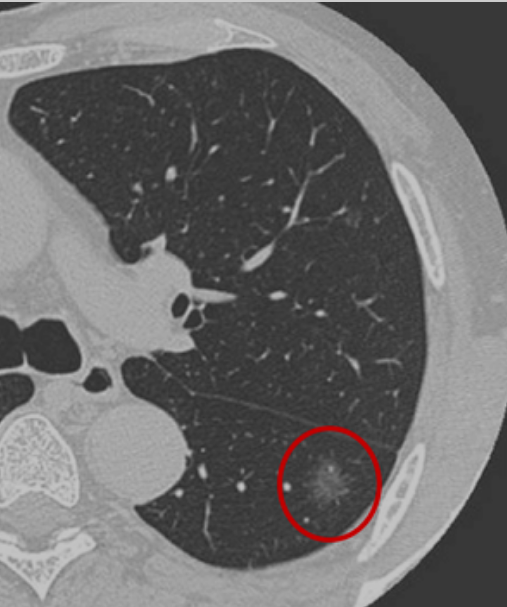

根据胸部CT判断是否存在磨玻璃密度成分,可将肺结节分为:纯磨玻璃结节、实性结节和部分实性结节。磨玻璃结节又叫磨玻璃影、毛玻璃结节等,表现为密度轻度增高的云雾状淡薄影或结节,在CT上跟磨砂玻璃一样。按病理性质,磨玻璃结节可以是良性病变如炎症或出血、局灶纤维化等,或者是癌前病变如原位腺癌、非典型腺瘤,也可以是恶性肿瘤如转移癌、微浸润腺癌等。

肺癌高危结节是指可能成为肺癌或转变为肺癌风险较高的肺结节,主要表现为直径≥1.5厘米或直径介于0.8至1.5厘米之间但表现出毛刺、分叶、胸膜牵拉、含气细支气管征和偏心厚壁空洞、空泡征等恶性CT征象的结节,以及直径大于0.8厘米的部分实性结节。此外,还需结合患者是否有肺癌家族史、长期吸烟史或患有其他恶性肿瘤病史等危险因素。高危结节通常需要经验丰富的影像科、肿瘤科、呼吸科或胸外科等医生进行综合判断。